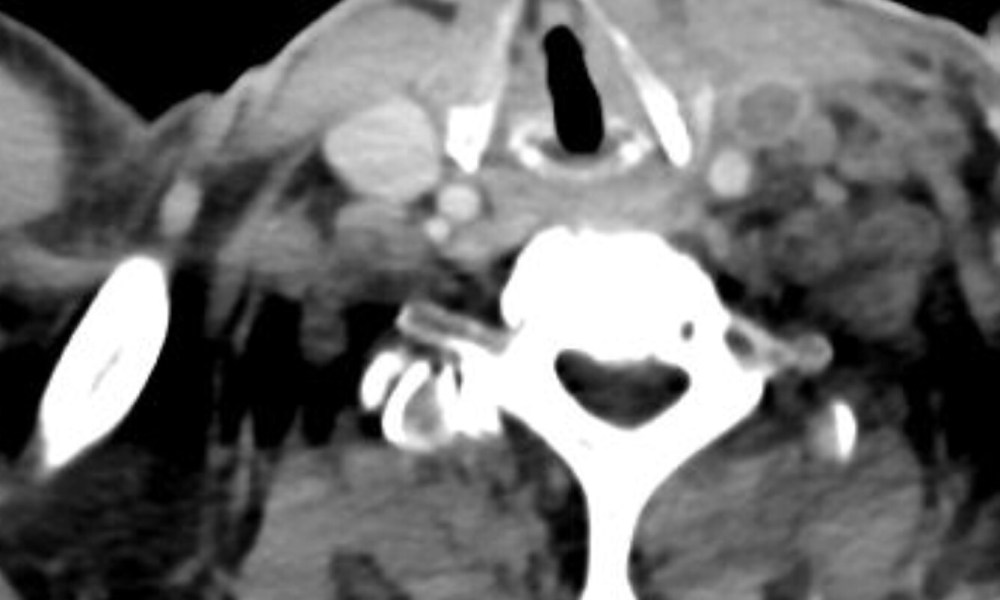

Investigations showed neutrophilic leukocytosis (WBC of 24K), cholestatic jaundice, as well as a high CRP of 217 mg/L CT of the abdomen was normal, but the following was seen at the neck and thoracic inlet.

The CT image showed thrombosis of the left internal jugular vein. Given the history of sore throat, fever with chills, as well as the findings of left neck tenderness and jaundice, the diagnosis is Lemierre’s syndrome, named after the French professor of bacteriology who described the clinical syndrome in a seminal Lancet paper in 1936. The most common cause of this disease is Fusobacterium necrophorum, although multiple other organisms can also cause internal jugular vein thrombophlebitis.